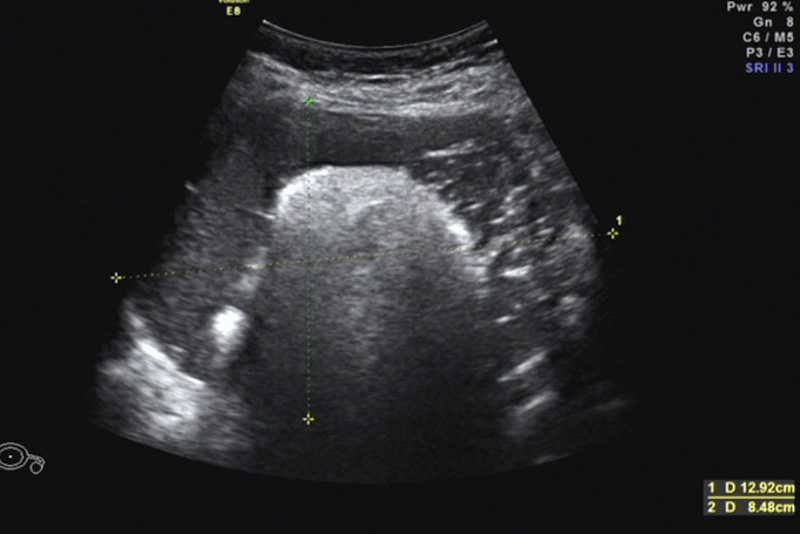

今年1月,石女士驚喜地發(fā)現(xiàn)自己懷孕了,然而在之后的孕檢過(guò)程中,檢查發(fā)現(xiàn)右附件區(qū)有一大小125mm×115mm×79mm囊性占位,混合回聲,考慮右側(cè)卵巢成熟畸胎瘤。由于囊腫巨大,內(nèi)部回聲雜亂,隨著孕期的增加,囊腫有可能發(fā)生扭轉(zhuǎn),導(dǎo)致破裂引起急性腹痛威脅母嬰安全。同時(shí),巨大的腹腔占位可能影響子宮增大,限制胎兒的生長(zhǎng)……

因患者腫塊巨大,孕期手術(shù)風(fēng)險(xiǎn)高,醫(yī)院立即組織了婦科、產(chǎn)科、放射科、超聲醫(yī)學(xué)科、麻醉科、藥學(xué)部等開(kāi)展了MDT會(huì)診。患者囊性占位中有大小約7cm的實(shí)性占位,手術(shù)需要考慮盡量減少手術(shù)后腹腔黏連,同時(shí)需要將占位完整切除,盡量減少對(duì)腹腔和子宮的干擾,才能最大程度保證孕期平穩(wěn)和母嬰安全,經(jīng)過(guò)全面考慮和深入討論,專家團(tuán)隊(duì)為患者制定了詳細(xì)的治療方案,決定行經(jīng)臍單孔腹腔鏡下行卵巢囊腫剔除手術(shù)。